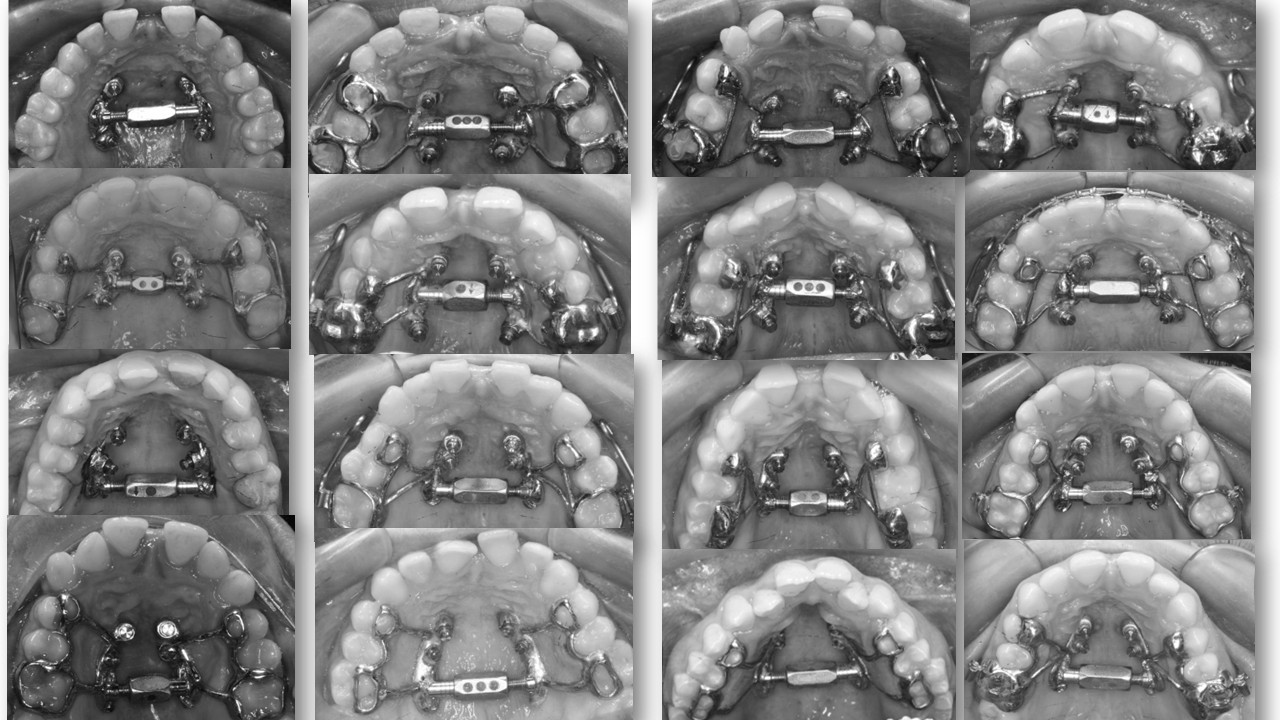

Anclaje esquelético MARPE guiado.

2. E EJECUCIÓN/EQUILIBRIO: Entre la ciencia y la sensibilidad. El ortodoncista moderno vive entre dos mundos: la tradición analógica y la revolución digital. Esta llave enseña a integrarlos. Ni rechazo tecnológico, ni dependencia ciega. EQUILIBRIO es criterio: usar lo nuevo sin olvidar lo esencial. “Lo digital no sustituye al criterio; lo amplifica cuando el juicio clínico está formado.”

MARPE en adultos / Miniplacas Clase III.

3. XCROSS/EXPANSIÓN: La tercera llave es la integración. Cuando biomecánica, cirugía y tecnología se alinean, los límites desaparecen, se amplian las fronteras. Ni la edad ni la complejidad son barreras cuando hay protocolo guiado. Lo que antes era imposible, hoy se resuelve con confianza.

MAPE en adultos y MISMARPE.

Clínico e investigador nos abrirá las puertas del MAPE en adultos con y sin asistencia quirúrgica con protocolos basados en la eficiencia clínica sin complicaciones.